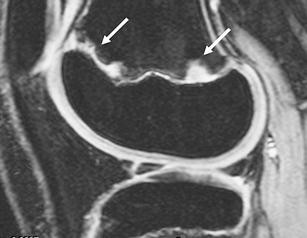

Fig. 3